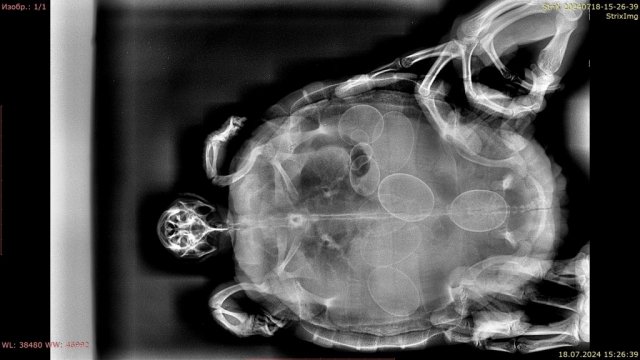

Консультанты moth Ваше имя: Мария Локация: Москва Опубликовано: 16 августа 2019 Консультанты Опубликовано: 16 августа 2019 (изменено) @Инна Г Если она крутится, плавает и держит голову преимущественно в одну сторону, то это поражение мозга на противоположной стороне. Скорее всего, геморрагический инсульт, вызванный травмой. Но это никак не проверить из-за её размера. Если это так, то оно либо само пройдёт либо останется вот так, либо будет проявляться в виде эпилепсии и т.д. Вам нужно уровень воды оставить такой, чтобы она не могла утонуть в припадке, но могла перевернуться в воде, если вдруг упадёт на спину. крен может быть либо отдельным симптомом той же пневмонии или переедания, либо следствием травмы. Лечить такую маленькую черепаху должен врач. У Васильева, по-моему, в субботу должен быть приём в Клыке. если приём не скоро, то можно сделать укол Дексафорт 0.01мл в мышцу попы, он снимает отёк Изменено 16 августа 2019 пользователем moth

Инна Г Ваше имя: Инна Локация: Москва Опубликовано: 16 августа 2019 Автор Опубликовано: 16 августа 2019 (изменено) Да у нее вроде травмы и не было, она ниоткуда не падала точно... Вчера еще утром за рыбами охотилась, очень резво плавала., а к вечеру ее перекосило... Может, свернула себе что-то в погоне? но думаю, что это маловероятно. Она меня в пластиковом контейнере маленьком пыталась укусить при кормлении, я руку отдернула и она немного ударилась о бортик. Но удар был очень слабый для травмы и тем более для инсульта. Сейчас уже вроде не крутится, просто плавает с креном и головой на бок...но очень мало, все лежит и греется под лампой. Записались на прием в зоопарке к Е.Ю.Дягилец на воскресенье, Васильеву не дозвонилась Изменено 16 августа 2019 пользователем Инна Г